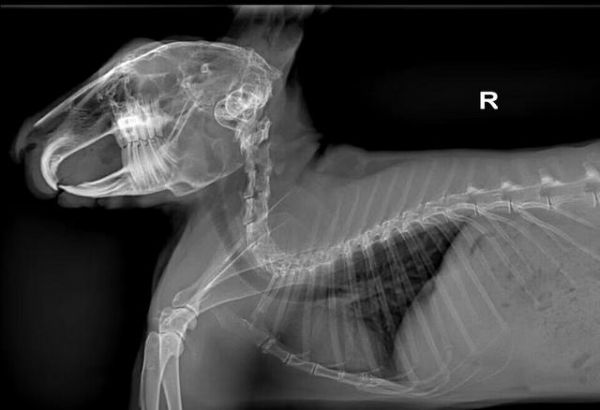

是哺乳类兔形目兔科下属所有的属的总称。俗称兔子。生物学分类动物界脊索动物门 脊椎动物亚门 哺乳纲 兔形目。

兔具有管状长耳(耳长大于耳宽数倍),簇状短尾,比前肢长得多的强健后腿。共9属43种。以亚洲东部、南部、非洲和北美洲种类最多。陆栖,多见于荒漠、荒漠化草原、热带疏林、干草原和森林或树林。

兔子嘴巴分上、下唇,其中上唇有纵裂(又称豁嘴),门齿外露,口边有触须。上唇中间分裂,是典型的三瓣嘴,非常可爱。除了有两颗向外突出的大门牙,兔共有28颗牙齿其余的都在口腔内部臼齿用做切碎草类。你是不是很震惊呢!